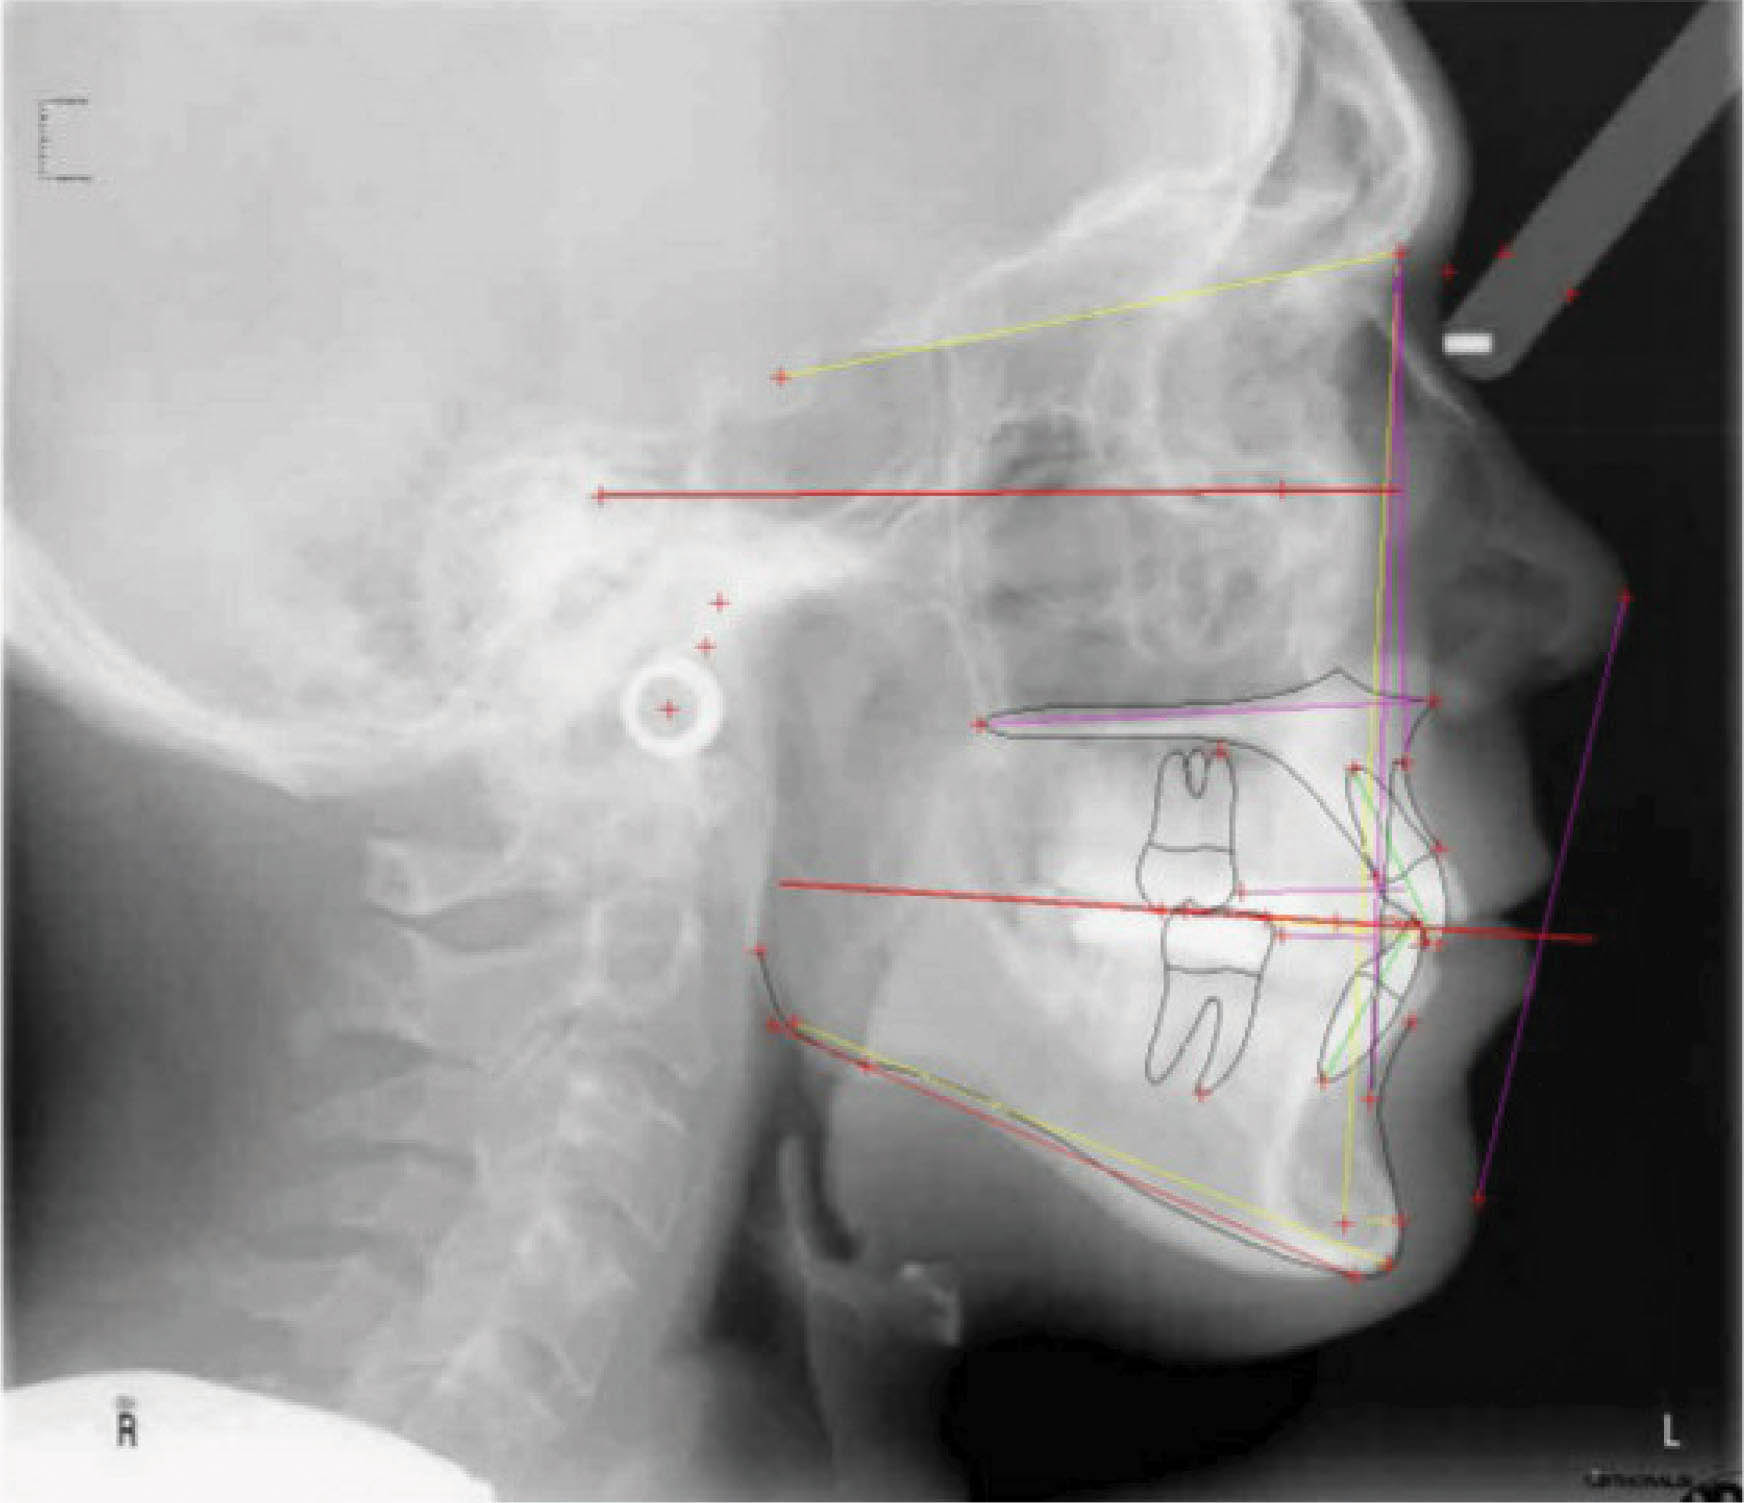

با سوپرایمپوز کردن لترال سفالومتری در شکل 35-6 شاهد سه درجه پروترود شدن انسیزورهای پایین هستیم. ارتفاع عمودی ثابت ماند و کنترل خوبی در حفظ زاویه پلن مندیبل داشتهایم. رادیوگرافی OPG پایان کار (شکل 36-6) طبیعی است. مدت نگهدارنده ۳۰ ماه بود و همه چیز خوب حفظ شده است (شکل 37-6).

شکل 35-6